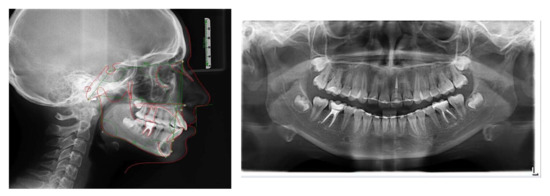

A 11-year-old patient presented to the private practice with her parents with a chief complaint of an unattractive smile, mainly due to an upper canine. The facial analysis showed an hypodivergent facial type with a reduced lower-third of the face, a convex profile with mandibular retrusion and upper lip protrusion with a proper nasolabial angle (Figure 1). The mini-esthetic analysis showed a superior inter-incisive line not coinciding with the median of the face, migrated on the left side, a ratio between arch amplitude and amplitude of the smile in the norm, and a reduced exposure of the smile with an irregular and asymmetrical smile arc. The intraoral clinical analysis revealed sagittal relationships of molar class II and canine class II, an upper interincisive line migrated on the left side, decreased transversal development of the upper arch, a severe crowding in the upper arch with a lack of space for 1.3 alignment, a 6.5 mm overjet, a 3.5 mm overbite, and an increased Spee curve (Figure 1 and Figure 2). The patient asked for treatment because the upper right canine (UR3) was not aligned and ectopic in the upper arch. Panoramic radiography and lateral cephalogram were required to confirm the diagnostic hypothesis of class II malocclusion and to measure incisors proclination. The cephalometric analysis showed a skeletal class II, hypodivergence and proclination of the upper and lower incisors (Figure 3, Table 1 and Table 2).

Figure 3.

Pretreatment radiographs and cephalometric analysis.

Figure 5.

Radiograph post Herbst and cephalometric analysis.

Figure 7.

Post-treatment radiographs and cephalometric analysis.